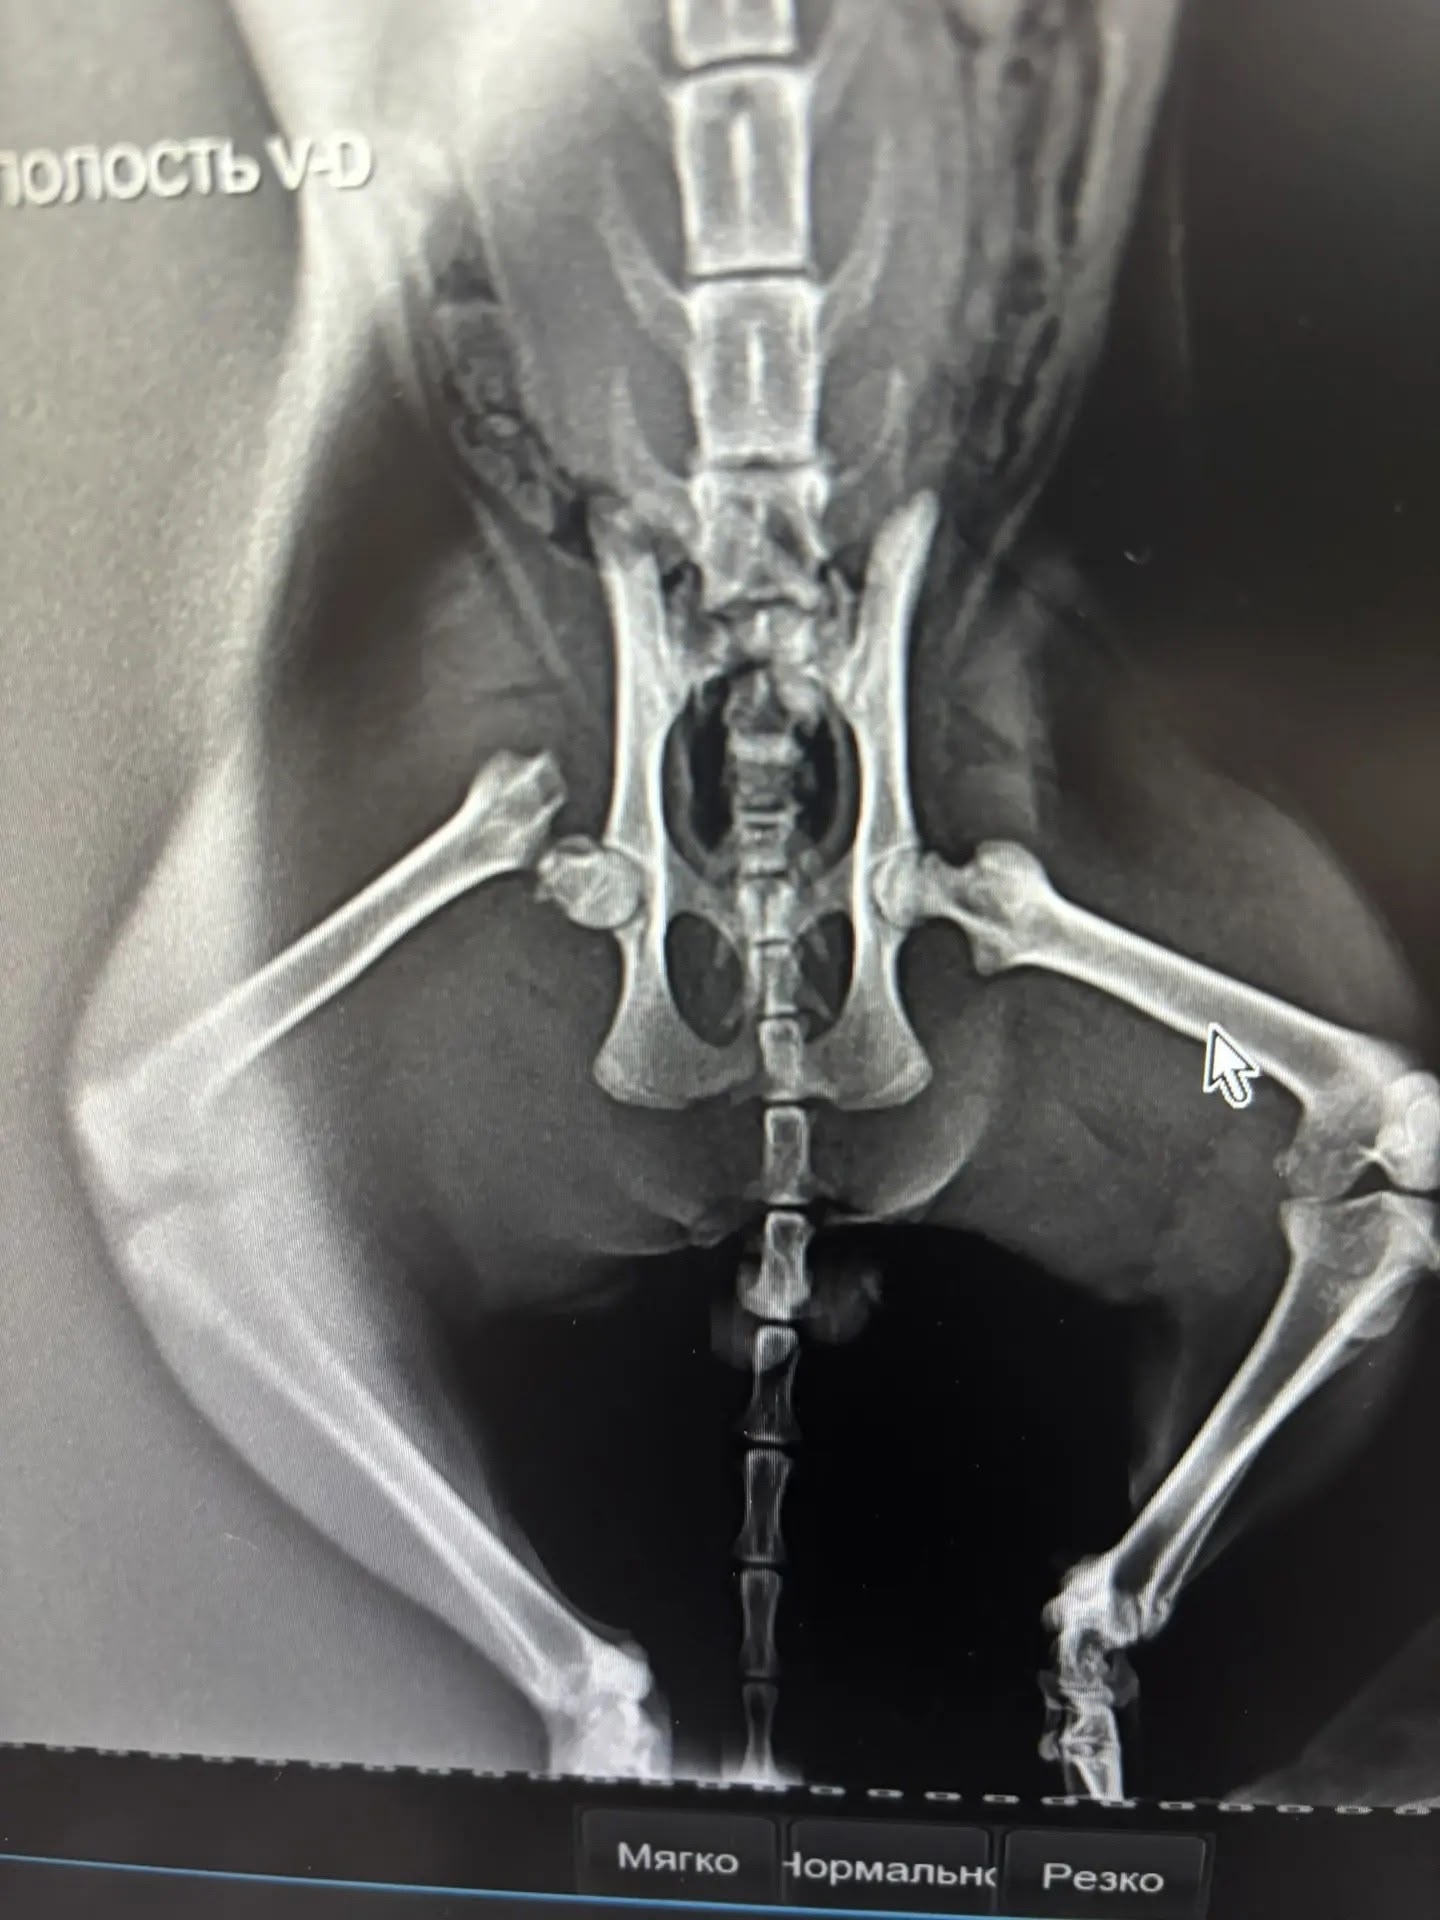

Вот у нас опять новенький с очень большой проблемой со здоровьем! Несколько дней кот лежал на одном месте (район школы N 9), даже невозможно представить сколько раз мимо проходили люди и всем было все равно! Равнодушие- страшное и такое современное слово! Его заметила женщина, кормила и поняла, что кот болен, забрала себе, но, к сожалению, финансово ей не осилить такие расходы и было принято решение забрать котика в приют. Назвали Дым, котик очень ласковый и есть маленькая надежда, но что он- потеряшка. Сдали анализы, сделали рентген- перелом шейки бедренной кости. Есть шанс встать котику на лапы, но для этого нужна огромная для приюта сумма -11 000 рублей, а еще анализы и рентген - 8 600, а у нас еще не закрыт сбор на стерилизацию Чернышки и куча финансовых расходов каждый день! Ну вот закидайте нас помидорами, но мы не могли поступить иначе! Операция уже 1 мая и осталось буквально несколько дней, и мы боимся, что не успеем собрать нужную сумму и котик Дым, возможно, уже никогда не встанет на лапки, если мы не успеем! Помогите нам, пожалуйста! Без вашей помощи Дым навсегда останется инвалидном без шансов найти дом!